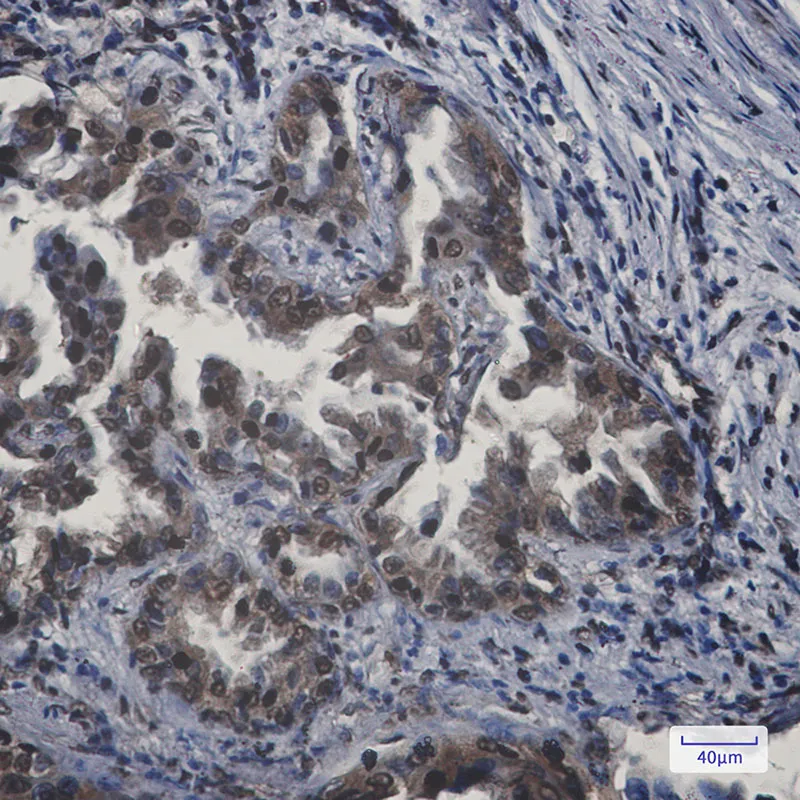

Annexin VII Rabbit Monoclonal Antibody

Cat: AMRe01652

Size1:50μL Price1:$158

Size2:100μL Price2:$288

Size3:500μL Price3:$1200

Application:WB,IHC-P

Reactivity:Human,Rat

Conjugate:Unconjugated

Gene Name:ANXA7

Size2:100μL Price2:$288

Size3:500μL Price3:$1200

Application:WB,IHC-P

Reactivity:Human,Rat

Conjugate:Unconjugated

Gene Name:ANXA7